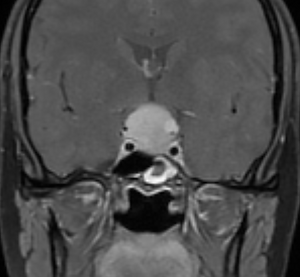

Tuberkulum sella menenjiomu

Tuberculum sella menenjiomu hipofizin hemen ön tarafındaki planum dediğimiz alandan büyüterek önce koku alma sinirlerine arkada da hipofize doğru baskı yapan menenjiomlardır.

Tuberkulum sella menejiomlarını hipofiz adenomlarında ayırt etmek kolaydır. Dural tail bulgusu, menenjiomların kontrastlanma paterni ve hipofizin nasıl itildiği konusunda tecrübe sahibi iseniz kolaylıkla iki tümörü birbirinden ayırt edebilirsiniz.

Tuberkulum sella menenjiomları genellikle sert olur ve beyinde görme sinirlerine ve anterior kommunikan arter dediğimiz önemli bir damara yapışık olurlar.